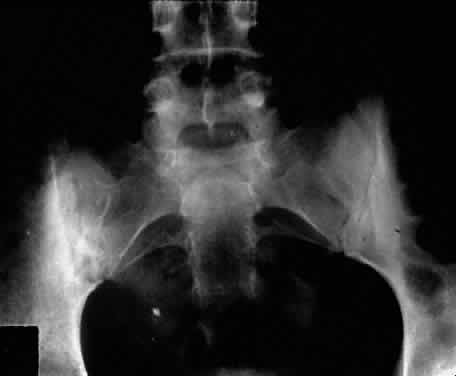

Ankylosing spondylitis is distinctly different from rheumatoid arthritis, although earlier literature did not make this distinction. The sacroiliac joint is usually the most easily visible area of involvement and is best seen in oblique views on radiography of the sacroiliac joint as periarticular sclerosis and irregular loss of the joint space. These patients are seronegative for rheumatoid factor and may have an elevated erythrocyte sedimentation rate.3,6 The presence of HLA-B27 antigen in 90% to 95% of white patients and 50% of black patients with ankylosing spondylitis is well documented, and the genetic predisposition to this disease has been recognized for many years. The relationship, however, is still incompletely understood at this point. HLA-B27 antigen is present in 6% to 14% of the white American population and 3% to 4% of the black American population. It is clear that people with this HLA type are at greater risk of developing one of the spondyloarthropathies, particularly ankylosing spondylitis, but as yet poorly defined environmental factors must be involved in triggering the development of the disease process.3,8 The development of acute iridocyclitis is even more strongly correlated with HLA-B27 antigen than is its association with joint changes. Of patients with HLA-B27 antigen, 20% to 25% will develop symptoms or radiographic evidence of spondylitis at some time in their life, and milder forms of the disease are commonly not diagnosed but believed to be due to back “strain” or injury. The incidence of clinical spondylitis is about equal between men and women, but the disease tends to be milder and more difficult to diagnose in women; its prevalence appears to approach 2% in those in the North American population who are HLA-B27 positive and who have been studied. The mechanism of how HLA-B27 antigen is involved in this disease process is unclear. HLA determinants are located on chromosome 6. These determine cell surface markers that enable the immune system to recognize each cell as self. One theory that has been advanced suggests that the HLA-B27 antigen may be similar to antigens of the cell wall of certain exogenous agents or may be changed by the agents in a manner whereby the immune system has difficulty recognizing or responding appropriately to the agent or the altered HLA-B27 antigen. In one study, patients with ankylosing spondylitis had lower in vitro responsiveness of lymphocytes to Klebsiella antigens than HLA-B27-positive and HLA-B27-negative controls.9 Antisera to certain isolates of Klebsiella lysed the lymphocytes of HLA-B27-positive patients with ankylosing spondylitis, but not the lymphocytes of HLA-B27-positive or HLA-B27-negative controls. This suggests that perhaps some Klebsiella antigens cross-react with a gene product closely associated with HLA-B27 or a Klebsiella-modified B27 antigen in patients with ankylosing spondylitis. Cross-reacting antigens have been identified in HLA-B27 and Klebsiella, Shigella, and Yersinia.10 The role of Klebsiella has not been clarified, and no other agent has been substantiated with respect to ankylosing spondylitis. Chlamydia has been suggested in some cases of Reiter's syndrome, especially in instances of nonspecific urethritis.11–13 Shigella, Salmonella, and Yersinia have been involved in clinical epidemics of postinfectious arthropathies.14 Additional theories involve HLA-B27 linkage with a specific immune response gene that predisposes patients to the disease, perhaps making them more susceptible to infection. The role of these factors remains to be clarified. The acute iridocyclitis associated with ankylosing spondylitis is characterized by rapid onset of pain, photophobia, and blurred vision. Conjunctival, episcleral, and scleral injection and edema are seen. Poorly defined keratic precipitates are seen in the lower half of the corneal endothelium, and the anterior chamber has heavy flare that may be uneven. If the process is severe, there may be clot formation in the pupil space.15,16 Cells in the anterior chamber may be so numerous that hypopyon will occur. Glaucoma can result from anterior chamber reaction blockage of the angle in the acute phase of inflammation and from pupil block from synechiae. Synechiae form early and, if not broken, will form lasting adhesions. Mydriatic and cycloplegic therapy is needed early in treatment. Spillover of inflammatory cells and inflammatory debris into the vitreous may occur, and the presence of disc blurring and macular edema is sometimes observed. This is sometimes also associated with hypotony. Posterior subcapsular cataracts and diffuse lens clouding are seen with severe prolonged episodes and repeated acute recurrences.15,16 The typical episode lasts from 2 to 6 weeks. Aggressive suppression of the inflammatory reaction with topical corticosteroids is usually sufficient and reduces tissue damage, if an early intensive schedule is used, rather than increasing the drop schedule as the reaction increases. These patients may need to be seen daily when they are acutely active and may need to be seen every 2 to 3 days until the process is stable or clearly resolving. Treatment must be continued for several weeks as the process is resolving or reactivation will occur. Oral corticosteroids can be given for short periods of time. Some patients experience elevation of intraocular pressure with corticosteroid therapy, particularly as the eye improves and the ciliary body is again more able to produce aqueous humor. The long-acting effects of periocluar injection of corticosteroids may become a more serious problem with persistent corticosteroid-induced glaucoma than the episode of acute iridocyclitis that was being treated. Frequent episodes of recurrent iridocyclitis may cause significant disability that results in loss of work, discomfort, and structural damage to the eye. These patients may benefit from longer term treatment with oral nonsteroidal anti-inflammatory agents, such as indomethacin or naproxen. These medications may help to reduce the severity and frequency of recurrences, but the pain-decreasing effects of these medications may make it more difficult for the patient to recognize an acute recurrence of the iridocyclitis. Patients should be examined for exacerbations of the inflammation if they note any change in vision, even minor symptoms. REITER'S SYNDROME OR POSTINFECTIOUS REACTIVE ARTHRITIS Reiter's syndrome is a clinical syndrome usually described as arthritis, conjunctivitis, or iridocyclitis and nonbacterial urethritis or cervicitis. A better definition may be needed, because not only may these not all be present, but also dysentery and mucocutaneous disease with balanitis, oral ulceration, or keratoderma blennorrhagicum may be part of the clinical picture. Enthesopathy of the plantar fascia or Achilles tendon is also suggestive of Reiter's syndrome. It is more commonly identified in males, but may be more frequent in females than previously thought.14 The incidence reported by Noer17 in US Navy personnel over a 10-year period was 4 in 100,000 men per year. HLA-B27-positive persons have approximately a 25% risk for Reiter's syndrome development after Shigella infection.18 Although the cause is unknown, the high correlation with the presence of HLA-B27 (75%)19 is clearly recognized. The previous discussion in the section on spondyloarthropathies concerning this HLA-B27 association demonstrates a genetic predisposition in a high percentage of these patients. In Reiter's syndrome, infectious agents are suggested by reports of clinically indistinguishable acute disease after epidemic dysentery and sexually transmitted nongonococcal urethritis thought to be due to Chlamydia20 or possibly Mycoplasma (Ureaplasma urealyticum).21,22 Large epidemics of dysentery have been linked to multiple occurrences of arthritis, urethritis, and iridocyclitis.17,23 Shigella, Campylobacter, Salmonella, and Yersinia have all been implicated.24 Microbial antigens have been identified in the synovium after infectious with Chlamydia, Yersinia, and Salmonella.25–27 Salmonella typhimurium is a frequently associated Salmonella pathogen causing reactive arthritis. This seronegative arthritis usually involves larger joints and the weight-bearing joints of the lower extremities. The knees and ankles are most frequently involved, with redness and diffuse swelling. Multiple joint involvement is usual. Periostitis and tendinitis may occur, especially involving the Achilles tendon, producing heel pain. Sacroiliac radiographic changes are present in up to 32% of patients.14 Children may be affected rarely.28 Reiter's syndrome tends to affect young adults in the range of 16 to 40 years of age. The diagnosis is sometimes hard to establish because the urethritis or cervicitis may be forgotten or suppressed and the enteritis and other symptoms may have been mild or not identified as abnormal. If a urethritis or cervicitis is present, cultures should be considered to make sure no treatable organism is present, such as gonococcus. Serologic testing for syphilis will help to rule out this sometimes-associated venereal problem. Low back pain due to insertional tendinitis and sacroiliitis is common. The dermal lesions typified by keratoderma blennorrhagicum, described as a hyperkeratotic erythematous dermatitis resembling pustular psoriasis, may not be present until later in the disease. It usually involves the hands and feet but may involve other areas. Superficial ulcers of the mucous membranes are frequent.29 Enteritis is usually a prolonged diarrheal episode with frequent passage of bloody, loose stools, but it may be a 24-hour episode of increased bowel activity.29 The conjunctivitis is usually described as mucopurulent and may be sterile. It may be accompanied by an iridocyclitis, episcleritis, or scleritis. Punctate and subepithelial corneal involvement has been reported. The iridocyclitis may be the presenting ocular manifestation. Recurrences are usually associated with an acute iridocyclitis, which is of rapid onset with conjunctival and episcleral edema and injection. The corneal endothelium has cellular debris and poorly defined, small-sized to medium-sized keratic precipitates.30 Heavy flare and cells and a very early tendency toward formation of posterior synechiae is characteristic, more so than in most other forms of acute iridocyclitis (Figs. 1, 2, and 3). Even the most aggressive pupil dilation management is sometimes inadequate for preventing synechiae. A peripheral iridectomy may be necessary to prevent iris bombé and angle closure if the synechiae cannot be broken enough to establish an opening for aqueous through the pupil (Fig. 4). The heavy flare is sometimes so plasmoid that cells are immobile and a fibrinlike clot may be seen in the pupil opening as the inflammation resolves. Cells and inflammatory debris may be seen in the vitreous, and blurring of the disc margins and macular edema may occur with severe or prolonged episodes. Lens clouding and posterior subcapsular cataracts occur with prolonged or repeated episodes. Hypotony can occur after a severe or prolonged course and may persist after resolution. Occasionally, secondary glaucoma may occur, owing to the anterior chamber reaction, in which case it will resolve as the inflammation resolves. With repeated recurrences, damage to the trabecular meshwork may occur, and prolonged recalcitrant glaucoma may result that may be poorly responsive to any medical or surgical management. This can be a serious factor in permanent visual loss with this type of iridocyclitis.15,16,30,31

unknown.32–35 The associated arthritis and iridocyclitis, however, are similar in both conditions. Peripheral arthritis is seen in approximately 12% of patients with ulcerative colitis and approximately 20% of patients with regional enteritis. Radiographic evidence of sacroiliitis has been reported to show an incidence of approximately 18% and to be equal in both sexes in both conditions. Clinical spondylitis is seen in association with bowel inflammation in 4% to 7% of these conditions. The overall incidence of HLA-B27 in these two conditions may be slightly elevated, but is similar to that in the normal population. HLA-B27 is present in 53% to 75% of patients who have both spondylitis and inflammatory bowel disease. The sacroiliac involvement is frequently asymmetric (Fig. 5). It is not clear whether the spondylitis is secondary to the inflammatory bowel disease or to an overlap of the conditions. Spondylitis occurs before the bowel disease in 25% of patients, and there seems to be little correlation in the activity of symptoms between the sacroiliitis and the bowel disease. Colectomy does not affect the sacroiliitis, even when the bowel disease is improved. This is in contrast to the activity of the peripheral arthritis, which does seem to parallel the activity of the inflammatory bowel disease in 60% to 74% of patients. The peripheral arthritis also precedes the bowel disease in 7% to 11% of patients.33,36,37 It is not clear how these relate to the associated iridocyclitis.